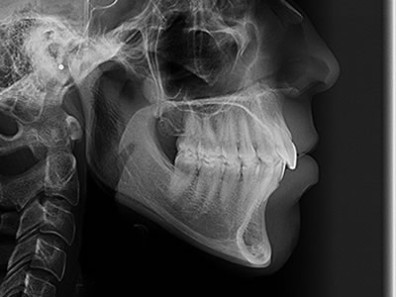

A telerradiografia lateral é uma radiografia do crânio padronizada e reproduzível. A técnica radiográfica extra-bucal permite a avaliação das relações entre os elementos dentais e os maxilares, e dos maxilares com o esqueleto facial, podendo assim avaliar os desvios de planos oclusais e alterações pertinentes às intervenções ortodônticas, ortopédicas e cirúrgicas.